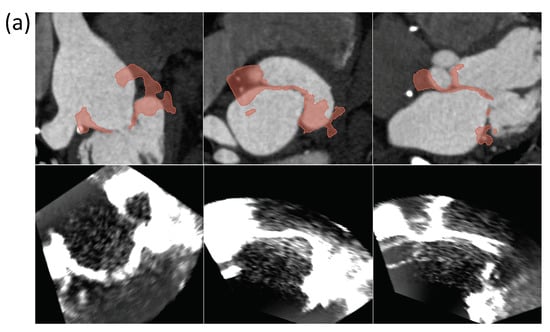

3.1. Case Study 1: Landmark Registration in Cardiology

3.1.2. CT/US Spatial Registration

3.1.3. Landmark Registration Optimization

4.1. Case Study 1